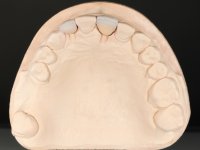

Paciente do sexo feminino, com 47 anos não fumadora. Apresentou-se na consulta com o dente 1.3 com tratamento endodôntico e com um espigão falso coto fundido, reabilitado com uma coroa provisória. Os dois incisivos laterais superiores são conoides e de reduzida dimensão. O dente 2.2 apresenta mobilidade, consentânea com uma significativa reabsorção óssea entre o dente 2.1 e o dente 2.3 Os dois incisivos centrais estão separados por um diastema de 3mm e o dente 2.3 apresenta uma oclusão cruzada com o dente antagonista. Verifica-se também a ausência de alguns dentes posteriores e uma higiene oral razoável. Na segunda intervenção realizada passados 8 anos, verificou-se que os incisivos centrais superiores se apresentavam cromaticamente mais escuros e apresentavam um sulco longitudinal no esmalte que estando pigmentado comprometia esteticamente o sorriso. O trabalho realizado na primeira fase do tratamento mostrava-se competente estética e funcionalmente. Por fim, um ano após a última intervenção, a paciente apresentou-se com uma fratura da faceta colocada no dente 2.1 provavelmente em resultado de estar em contacto com o coto do implante. A rigidez da anquilose implantar, pode ter sido a causa desta fratura. Outros casos deste tipo de fratura já foram observados por mim em situações clínicas idênticas. A faceta do dente 1.2 apresentava-se esteticamente comprometida e a própria estrutura dentária apresentava uma pequena cárie e, pelo que se recomendaria a sua substituição.

O tratamento iniciou-se com a re -preparação do coto do espigão falso coto fundido, com o objetivo de colocar as linhas de acabamento cervical com uma localização intra-sulcular e simultaneamente confecionar uma coroa provisória adaptada. Com um tratamento ortodôntico muito simples, fechou-se o diastema entre os incisivos centrais superiores e estabilizou-se esta posição com um arame colocado na superfície palatina dos centrais, funcionando como contenção. Posteriormente procurou-se fazer uma tração ortodôntica lenta do dente 2.2 com o intuito de diminuir, ainda que muito ligeiramente a perda óssea vertical nessa zona. Finalizada a tração, foi feita a extração do dente 2.2 e a zona foi reabilitada provisoriamente com uma coroa de resina composta colada aos dentes adjacentes. Foi colocado um implante dentário na zona do dente 2.2 sendo novamente colada a coroa provisória em resina, reabilitando provisoriamente a paciente durante o período de osseointegração. No dente 1.3 foi feita uma gengivectomia com bisturi elétrico, com a intenção de subir o nível cervical do 1.3 conseguindo uma maior harmonia com o dente 2.3. Estabilizados os tecidos moles, foi feita uma impressão com a técnica de moldeira aberta, utilizando silicones de adição de consistência “putty” e “light”. A recolha da cor, tanto da componente dentária como dos tecidos moles foi feita pelo ceramista no consultório.  No laboratório as impressões foram passadas a gesso e deram origem a modelos de trabalho que foram devidamente analisados. Foi decidido confecionar um “abutment” metalo-cerâmico aparafusado sobre o implante. Este “abutment” foi fundido com uma liga nobre e posteriormente revestido a cerâmica coronária e gengival. Dada a inclinação do implante o aparafusamento condicionou de forma inevitável a saída do orifício do parafuso pela superfície vestibular. No sentido de esconder esta situação, o desenho do “abutment” já foi idealizado com a intenção de acomodar na superfície vestibular a colagem de uma faceta feldspática. Este “abutment” foi provado em boca e foram feitos ajustes no componente cerâmico gengival. A sua adaptação aos tecidos moles foi feita tanto de forma subtrativa, com broca, como de forma aditiva, acrescentando resina composta de tonalidade gengival. Este acrescento de resina seria orientador do ceramista na colocação final da cerâmica de tonalidade gengival. A coroa que reabilitaria o dente 1.3 foi cimentada nesta consulta de prova com cimento de ionómero de vidro reforçado com resina composta. Finalizado o trabalho em laboratório da faceta sobre o 1.2 e o “abutment” e a faceta para o implante este foi colado em boca, após a colocação do isolamento absoluto. O trabalho satisfez plenamente a paciente. Durante oito anos a paciente foi seguida regularmente, mostrando-se agradada com o tratamento efetuado, no entanto começou a mostrar interesse em intervir esteticamente nos incisivos centrais superiores. Decidida a segunda fase da nossa intervenção, foi feita a preparação dentária dos dentes 1.1 e 2.1 para a colocação de duas facetas feldspáticas. Particular cuidado foi tido na preparação inter-proximal distal junto ao “abutment” do implante. Foi preciso avaliar muito pormenorizadamente o eixo de inserção da faceta em relação ao “abutment”. As facetas feldspáticas foram confecionadas em laboratório e posteriormente coladas em boca após a colocação de isolamento absoluto. Um ano após, iniciamos a nossa terceira fase de tratamento, após a faceta colada no dente 2.1 ter fraturado. A preparação dentária foi feita sobre a faceta colada, procurando estender mais para palatino o interface inter-proximal distal. O objetivo seria passar para mais palatino do ponto de contacto o interface faceta-dente. O preparo dentário do dente 1.2 também foi muito reduzido, limitando-se a criar um eixo de inserção. Após confecionadas a coroa total e a faceta em laboratório foram coladas em boca. Primeiro foi colada a coroa utilizando-se um isolamento relativo com teflon, posteriormente foi colada a faceta após a colocação do isolamento absoluto. Na coroa utilizei este tipo de isolamento para evitar a utilização de grampos. Seria difícil de aplicar pela forma e dimensão do dente e agressivo para os tecidos moles. Após a colagem foi avaliada a integração oclusal do trabalho.